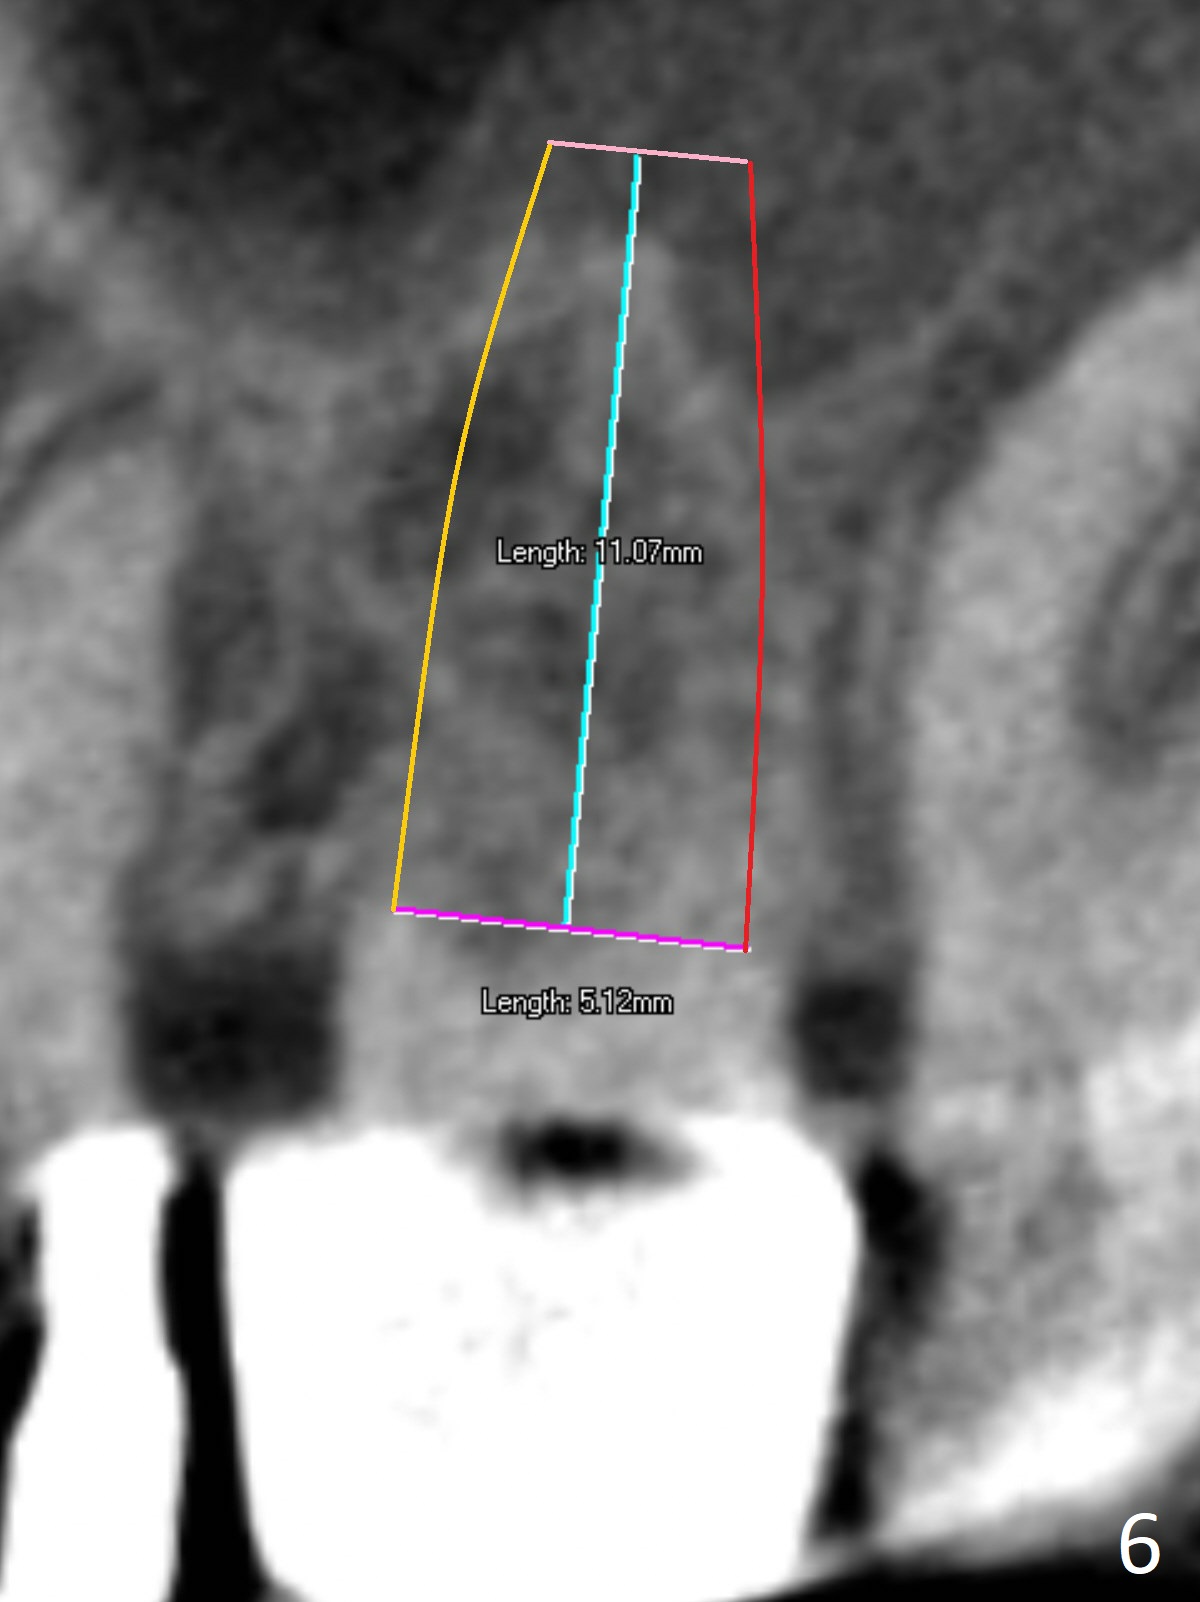

A 70-year-old woman fractures the crown at #14 (Fig.1). A 5x11 mm implant will be placed at the septum (Fig.2). Osteotomy depth can be determined using bony (Fig.3 with stopper) or gingival (Fig.4,5 with vision) landmark. The CT was taken 5 years earlier. Sagittal (Fig.6) and axial (Fig.7) sections confirm suitability of the 5x11 mm implant for the site. Prepare surgical handpiece for sectioning the tooth for extraction. After drills, use Magic Expanders for sinus lift. Place Vanilla Graft prior to dummy implant(s). A bone-level implant crown may be easier to be repaired if the proximal contact is not ideal.